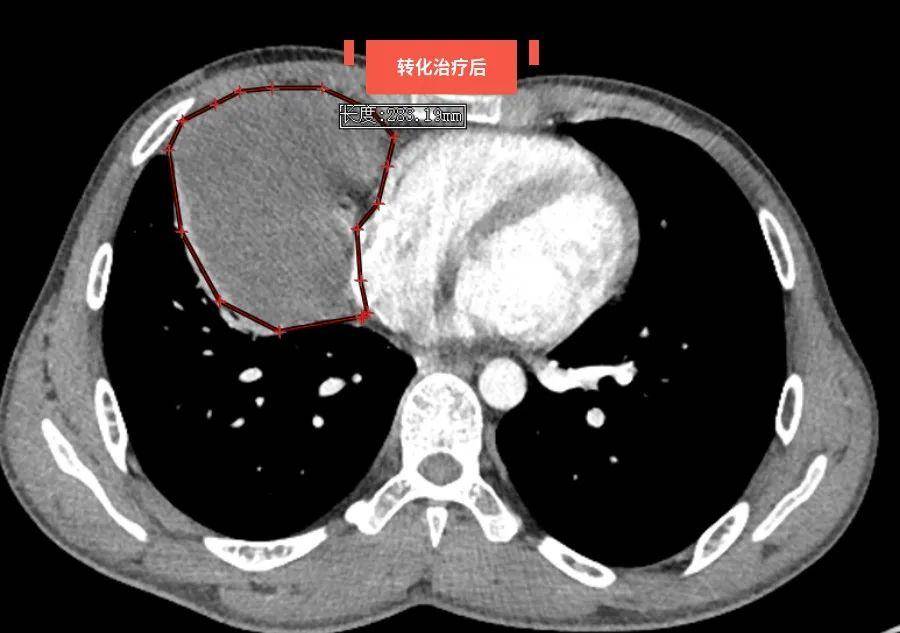

陈女士在一次意外事故中摔倒,当地医院ct检查提示纵隔占位(肿瘤),因

图片尺寸800x600